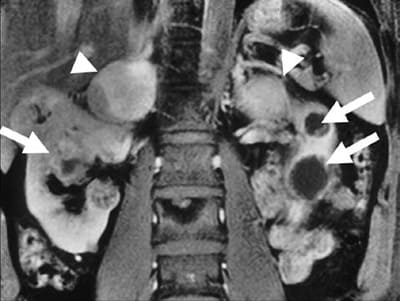

Сагиттальный снимок МРТ брюшной полости. Стрелками показаны двухсторонние феохромоцитомы надпочечников, в сочетании с карциномами.